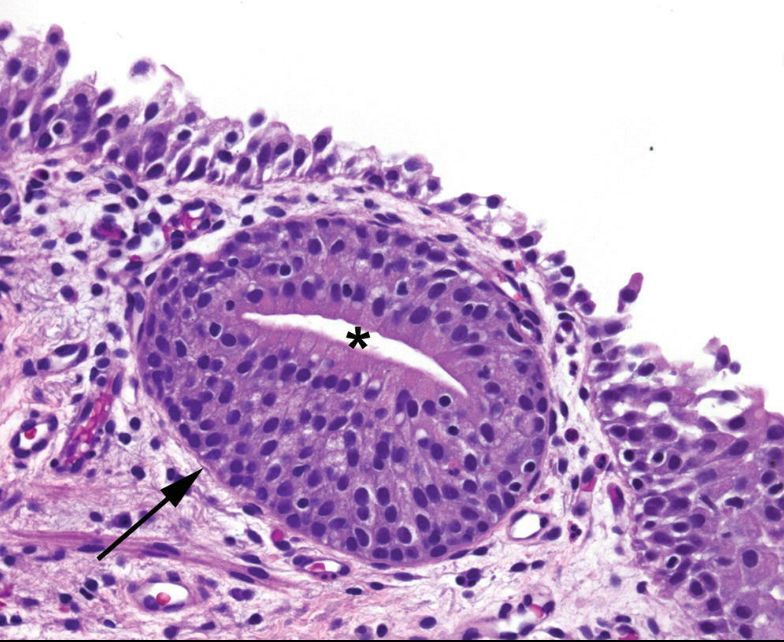

von Brunn’s nests

Invaginations of the normal urothelium into the lamina propria.

The center often acquires a lumen and columnar cell metaplasia (rather than umbrella cells). This variant is called cystitis glandularis (shown here).

Very common.